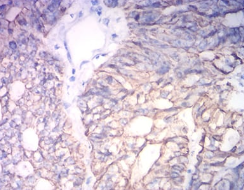

KRT19 Mouse Monoclonal antibody[2A1G9]

IHC    1/200 - 1/1000